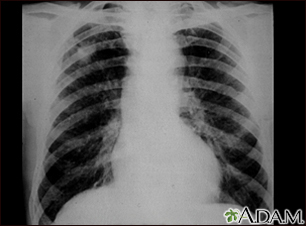

Coal workers pneumoconiosis - stage II